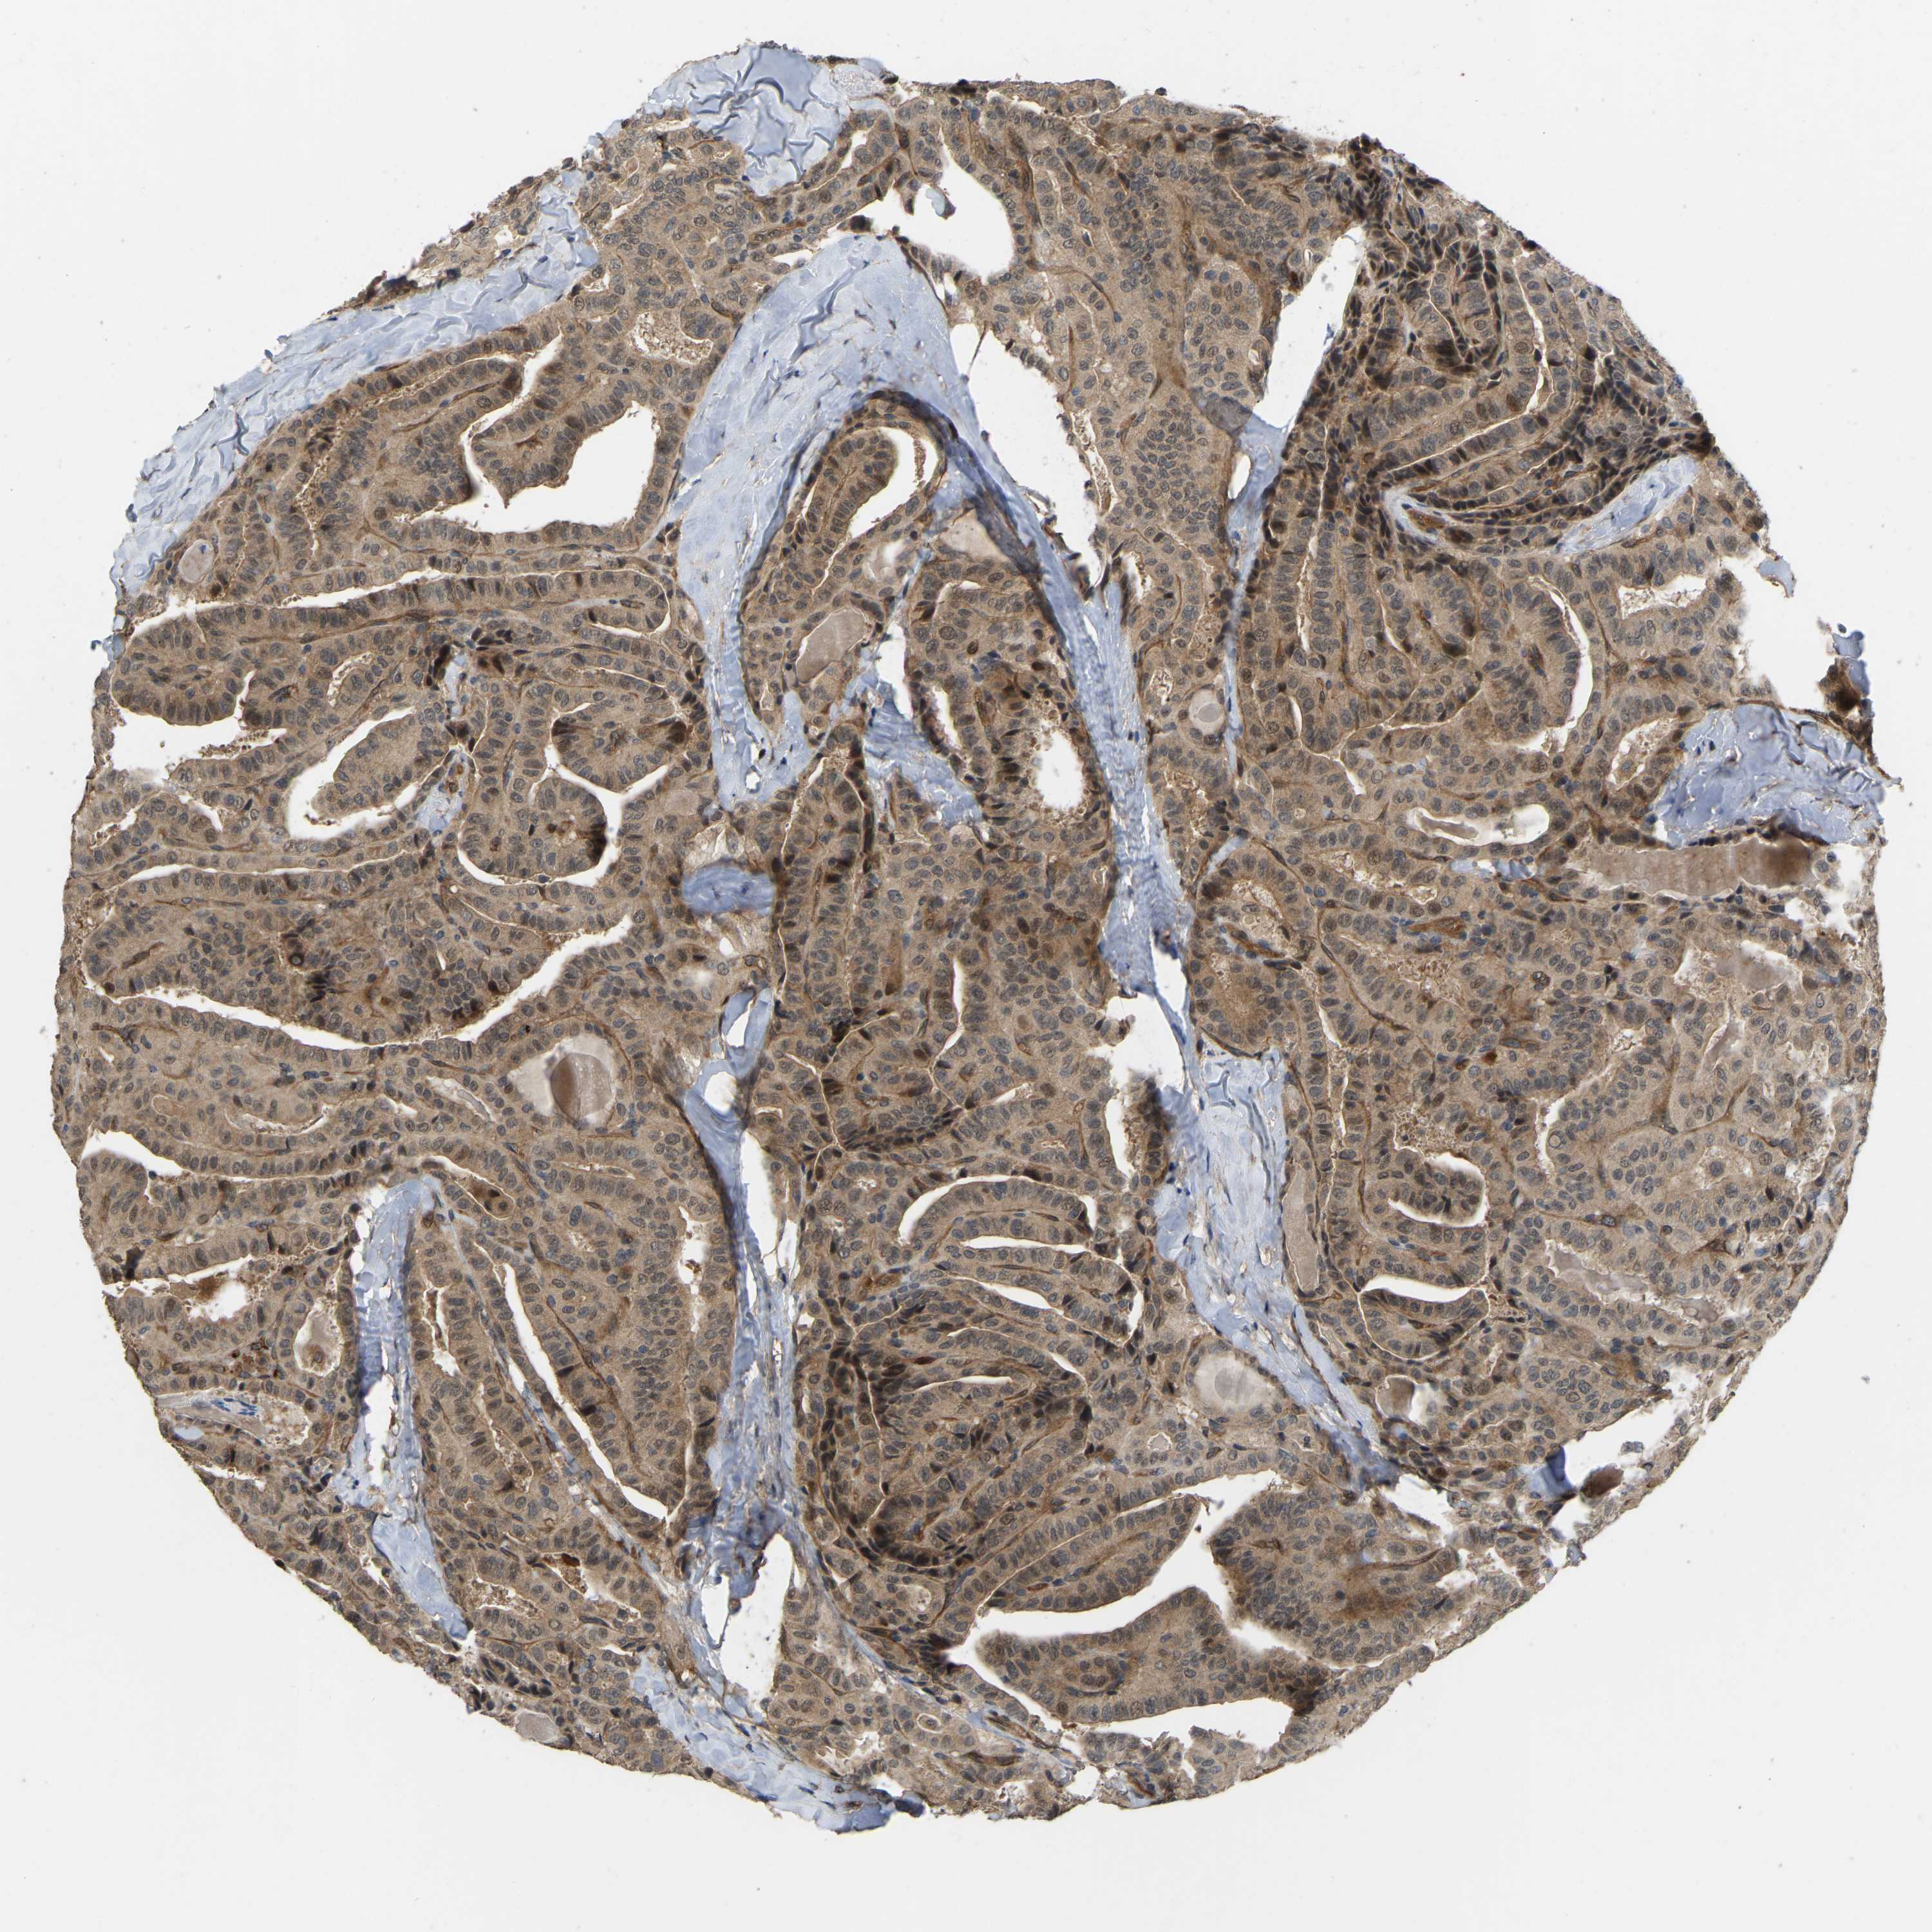

THYROID CANCER - Protein expressioni

A mouse-over function shows sample information and annotation data. Click on an image to view it in a full screen mode. Samples can be filtered based on level of antibody staining by selecting one or several of the following categories: high, medium, low and not detected. The assay and annotation is described here.

Note that samples used for immunohistochemistry by the Human Protein Atlas do not correspond to samples in the TCGA dataset.

Antibody stainingi

Antibody staining in the annotated cell types in the current human tissue is reported as not detected, low, medium, or high, based on conventional immunohistochemistry profiling in selected tissues. This score is based on the combination of the staining intensity and fraction of stained cells.

Each image is clickable and will lead to virtual microscopy that enables deeper exploration of all samples and also displays staining intensity scores, fraction scores and subcellular localization as well as patient and tissue information for each sample.

Antibody HPA008183

Antibody HPA053882

Antibody CAB019313

Staining

High

Medium

Low

Not detected

Intensity

Strong

Moderate

Weak

Negative

Quantity

>75%

75%-25%

<25%

None

Location

Nuclear

Cytoplasmic/membranous

Cytoplasmic/membranous,nuclear

Papillary adenocarcinoma, NOS

Follicular adenoma carcinoma, NOS